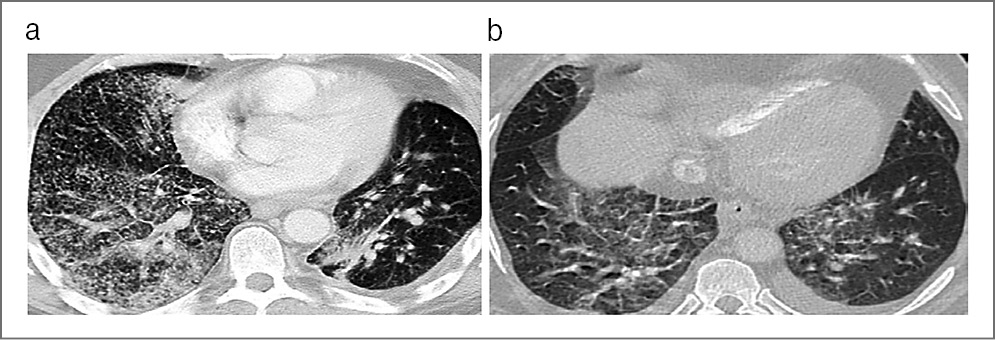

В качестве примеров приводим КТ органов грудной клетки, иллюстрирующую сходство КТ-признаков у больных 1 и 2-й групп, с этиологической верификацией бактериальной пневмонии (вызванной S. aureus) с COVID-19 (рис. 1, а) и без COVID-19 (рис. 1, b); микобактериозом легких (обусловленным M. avium complex) с COVID-19 (рис. 2, а) и без COVID-19 (рис. 2, b); пневмоцистной пневмонией (вызванной P. jiroveci) с COVID-19, ТОД (рис. 3, а) и без COVID-19 (рис. 3, b) и вирусной пневмонией (вследствие инфекции Cytomegalovirus hominis) с COVID-19, ТОД (рис. 4, а) и без COVID-19 (рис. 4, b).

Рис. 2. КТ органов грудной клетки. Аксиальная проекция, режим легочного окна: а – пациент, 28 лет, с 4B-стадией ВИЧ- инфекции в фазе прогрессирования, без АРВТ и верифицированной коинфекции COVID-19, ТОД и микобактериозом легких (вызванным M. avium complex); b – пациент, 32 года, с 4B-стадией ВИЧ-инфекции в фазе прогрессирования, без АРВТ и верифицированной коинфекции ТОД и микобактериозом легких (вызванным M. avium complex).